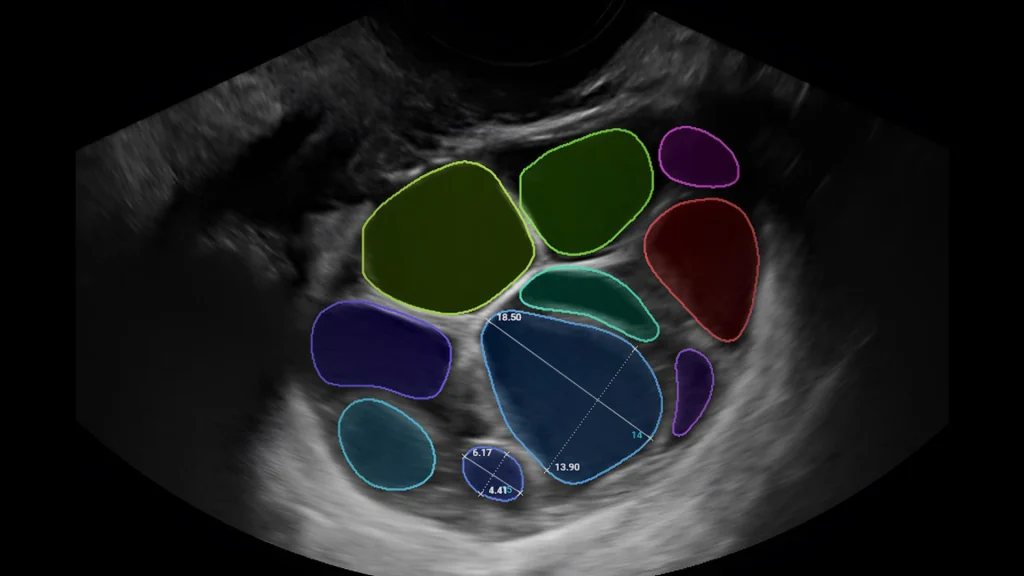

Folliscan:Inteligencia artificial en reproducción asistida

Cuando la inteligencia artificial se integra a la medicina reproductiva, no solo suma tecnología: aporta precisión, consistencia clínica y mejores herramientas para la toma de decisiones.

En Reprotec seguimos incorporando innovaciones que optimizan el manejo de la infertilidad. Por eso hoy somos el único centro en Colombia que cuenta con FOLLISCAN, un sistema basado en inteligencia artificial diseñado para el monitoreo de los folículos durante la estimulación ovárica.

Su integración nos permite:

Optimizar los tiempos de monitorización folicular.

Estandarizar criterios de medición dentro del equipo médico.

Fortalecer la toma de decisiones basadas en datos clínicos más precisos.